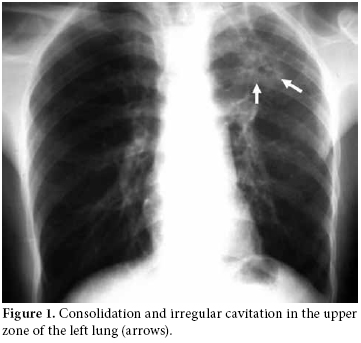

Consolidation and irregular cavitation in the upper zone of the left lung was detected in the chest radiograph (Figure 1); however, knee radiographs were considered normal. Magnetic resonance imaging of the right knee revealed inflammation in the knee, around the joint and in the superior tibiofibular articulation. The knee MRI also revealed centrally necrotic abscesses with peripheral enhancement of the rim after a gadolinium injection (Figure 2). An MRI of the right shoulder also showed increased inflammatory signal changes in the acromioclavicular joint and adjacent soft tissue with enhancement after gadolinium injection (Figure 3). The purified protein derivative (PPD) skin test for Tbc measured 22 mm. A synovial biopsy taken from the knee detected granulomatous inflammation with caseation necrosis. Antibiotic treatment with isoniazid, rifampicin, ethambutol and pyrazinamide were prescribed for two months followed by rifampicin and isoniazid for seven months. The patient showed significant improvement in the knee and shoulder within two months and close to complete improvement within six months.

Magnetic resonance imaging is the best modality to evaluate soft tissue affection by demonstrating marrow changes, joint effusion, synovitis, pannus, and cartilage and bone erosions.[2,16] Joint and periarticular involvement and lesions are particularly well defined by an MRI. The definitive diagnosis is performed from a positive mycobacterial culture and a histological examination of synovial fluid or synovial membranes. An examination of a biopsy specimen is an important and useful diagnostic method. Amplifying DNA of Mycobacterium tuberculosis from synovial fluid or bone by PCR could be useful for the early diagnosis of Tbc. We performed a definitive diagnosis through the histopathological examination of a synovial biopsy, a chest radiograph showing cavitation and the definitive demonstration on MRI examination. This was done in spite of the lack of positivity of mycobacterial culture and PCR. In addition, following the initiation of specific antituberculous treatment, the patient showed significant improvement in the knee and shoulder within two months with close to complete improvement within six months. We extended treatment to nine months in accordance with the recommendations for musculoskeletal tuberculosis in the literature and by the Turkey Ministry of Health.[17,18]